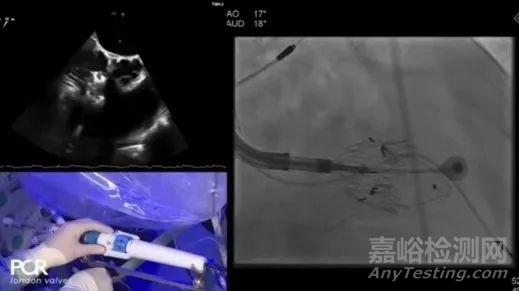

手術(shù)在全麻狀態(tài)下開展,采用經(jīng)右側(cè)頸靜脈入路的方式將輸送器送入患者心臟內(nèi),在TEE及DSA引導(dǎo)下調(diào)整輸送器頭端角度,使得輸送器與三尖瓣瓣環(huán)平面垂直。在輸送器進入右心室后釋放室間隔錨定裝置,而后釋放瓣葉夾持件(2個耳片結(jié)構(gòu))成垂直狀態(tài)。在TEE及DSA確定夾持件固定至三尖瓣葉根部且位于右室側(cè)后釋放人工瓣心房側(cè)盤片。隨后調(diào)整瓣膜同軸性以及室間隔錨定件位置(貼合室間隔),前推藏針管并固定,進而釋放室間隔錨定裝置,并再次確認瓣膜位置、穩(wěn)定性及同軸性,合攏輸送鞘后撤出輸送器,完成LuX-Valve Plus人工三尖瓣瓣膜的植入。

本例患者為75歲女性,術(shù)前經(jīng)CT和超聲心動圖診斷為重度TR(TR4+),患者三尖瓣瓣環(huán)偏大,右心功能尚可(RVEF為55.2%),右房室大小尚可,Coaptation gap大于8.5mm。心臟決策團隊綜合判斷患者不適合緣對緣經(jīng)導(dǎo)管三尖瓣修復(fù)技術(shù),決定使用創(chuàng)新TTVR MonarQ系統(tǒng)對該患者進行治療?;颊呓?jīng)過全麻處理后,經(jīng)頸靜脈將輸送器安全送入右心房。在右房完成調(diào)彎和初步瓣架釋放,調(diào)同軸后,在超聲和DSA指引下,快速起搏保護進入心室。在右室調(diào)整瓣架深度及角度,在多模態(tài)影像下調(diào)整瓣膜與瓣葉完全貼附,釋放瓣膜心房段,使原生瓣葉貼附在MonarQ瓣架中間,自然的順應(yīng)血流流動節(jié)奏。瓣膜釋放過程非常順利,術(shù)后超聲和造影驗證幾乎無返流,瓣膜位置形態(tài)極佳。患者返回病房后狀態(tài)良好,并在術(shù)后10天順利出院。